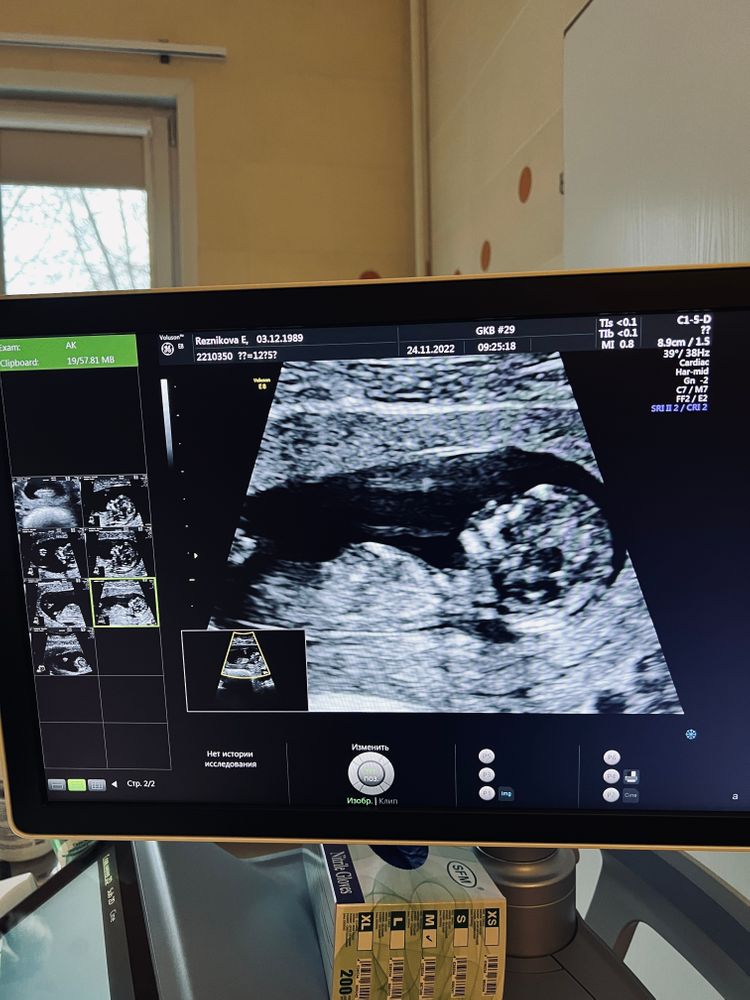

Ватная Даша, только на телефоне. На руки ничего не дали:( Изображение

Маргарита, узи на руки мне не дали, и в карте тоже его нет пока. Есть только фото со скрининга на телефон (я выше прислала)